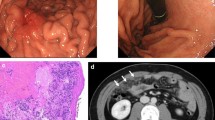

The clinical information of 18 patients with Hp-uninfected DGCs (median age 57 years; range 29–78) and nine subjects without Hp infection (median age 44 years; range 28–77) was collected (Table 1). Sixty-seven percent of patients with DGC had a smoking history, and 33% were current smokers (Table 2). Fifty percent of patients with DGC had alcohol consumption habit. Among the 18 patients, 16 were diagnosed with intramucosal DGC (median age 60 years; range 29–73) and two with advanced DGC. Sixteen intramucosal DGCs were found as flat pale areas upon endoscopy, all of which were resected endoscopically and were found to contain an SRCC component. One DGC localized in the gastric cardia consisted of a mixture of SRCC and PDA components (Fig. 1a and lower panels of Fig. 1b), and the remaining 15 DGCs localized near the gastric angle were ‘pure’ SRCCs scattered around the neck of the gland (Fig. 1a and upper panels of b). These intramucosal ‘pure’ SRCCs had a low proliferation capacity, with a median Ki-67 labeling index of 2.4% (range 0–15.4%). Five cases with intramucosal ‘pure’ SRCC showed no progression over 2–5 years according to endoscopic image review (Fig. 2).

Changes in endoscopic findings in Hp-uninfected intramucosal signet ring cell carcinoma over time. Top panels: endoscopic images of Case 8. A biopsy from a tiny pale area at the greater curvature of the gastric angle revealed an SRCC in the year 2018. After biopsy, the lesion became indistinct. In 2020, the lesion became visible, and the size of the lesion was almost the same as that observed in 2018. The second, third, fourth and fifth panels: endoscopic images of Cases 10, 16, 17, and 18, respectively. Upon retrospective review of the endoscopic images, SRCCs were found that remained unchanged for 5, 3, 2, and 3 years, respectively. Yellow arrowheads show the lesions. The number in the lower right-hand corner represents the year in which the image was taken

The median Ki-67 index of ‘pure’ SRCCs was 2.4%, which is similar to that in a previous report, indicating their low proliferative capacity [16]. Interestingly, five cases with ‘pure’ SRCCs whose endoscopic images could be reviewed showed no progression over 2–5 years. These results suggest that Hp-uninfected ‘pure’ SRCCs have an indolent feature that makes them less likely to become invasive. Yorita et al. also reported in a retrospective study that Hp-uninfected early SRCCs were less likely to be invasive cancers [17]. Furthermore, all 15 ‘pure’ SRCCs, including those that were not genetically analyzed, were located near the gastric angle and characterized by reduced E-cadherin expression. In animal studies, the loss of E-cadherin function due to Cdh1 deficiency resulted in the development of SRCC-like atypical cells, but it was not sufficient for invasive cancer formation [26, 30]. Factors such as chronic stimulation by Helicobacter infection or nitroso compounds and Trp53 mutations are required for the invasion of SRCC in Cdh1 knockout mice [26, 30, 36, 37]. The present study showed that 10% of advanced DGCs harbored both CDH1 and TP53 mutations in contrast to none of the CDH1-mutated intramucosal SRCCs harboring TP53 mutation. These results suggest that some CDH1-mutated intramucosal SRCCs become advanced DGCs with the addition of TP53 mutations, as shown in animal experiments [26, 36]. This hypothesis is supported by a study showing that p53 is not aberrantly expressed in intramucosal HDGCs, whereas its expression is altered in invasive HDGCs [38]. However, the discrepancy in the CDH1 and TP53 mutation frequencies between intramucosal and advanced DGC suggests that CDH1-mutated intramucosal DGCs make a relatively small contribution to advanced DGC formation in the Hp-uninfected stomach and that unknown TP53-mutated precancerous lesions might exist.